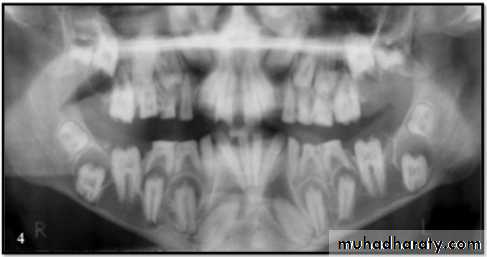

Dentin Dysplasia

Both dentitions are of normal color.

Periapical lesions.Premature tooth loss may occur because of short roots or periapical inflammatory lesions.

Radiographically:

Roots are extremely short.

Pulps almost completely obliterated.

Periapical radiolucencies:

granulomas

cysts

chronic abscesses

Type I (Radicular Type)

Dentin dysplasia, type I. panoramic & periapical films of the same case show the short and poorly developed roots, obliterated pulp chambers and root canals, and periapical inflammatory lesions.